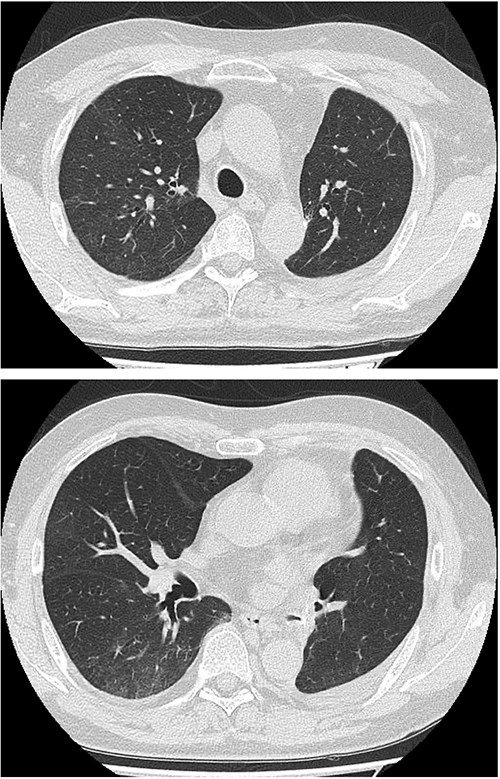

On POD 10, he developed fever and tested positive for COVID-19 by reverse transcription-polymerase chain reaction. Nosocomial transmission was suspected given recent ward cases during the delta variant outbreak. Chest computed tomography showed minimal peripheral ground-glass opacities in the right upper lobe (Fig. 2a and b). He received remdesivir (5 days) and dexamethasone (7 days), maintained adequate oxygenation without supplemental oxygen, and was discharged on POD 21 after clinical improvement.

Serial chest imaging demonstrating pulmonary complications. (a) Postoperative day (POD) 10: Initial presentation without significant abnormalities. (b) POD 16: Peripheral ground-glass opacities (arrowheads). (c) POD 27: Patchy consolidation (solid arrows) with new ground-glass opacities and pleural effusion (open arrows). (d) POD 36: Progressive consolidation (solid arrows).